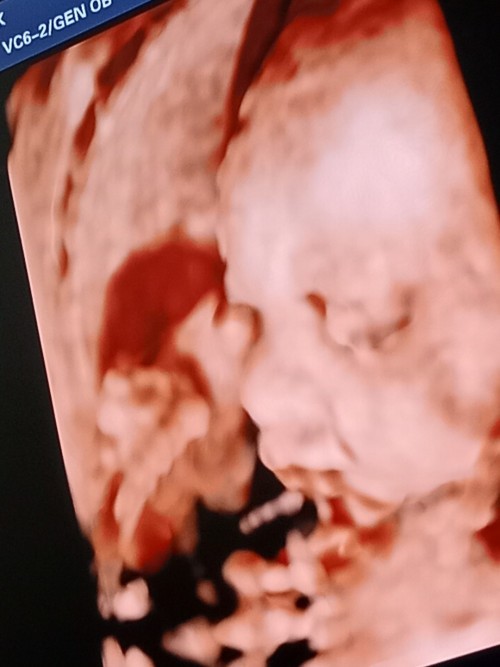

เอาภาพอัลตราซาวด์มาอวดจ้า บ้านนี้แลบลิ้นให้ป้าหมอไป1ที แถมเตะโชว์ไป1ที5555ป้าหมอบอกอาจจะดื้อนะ #ลูกสาว #ท้องแรก